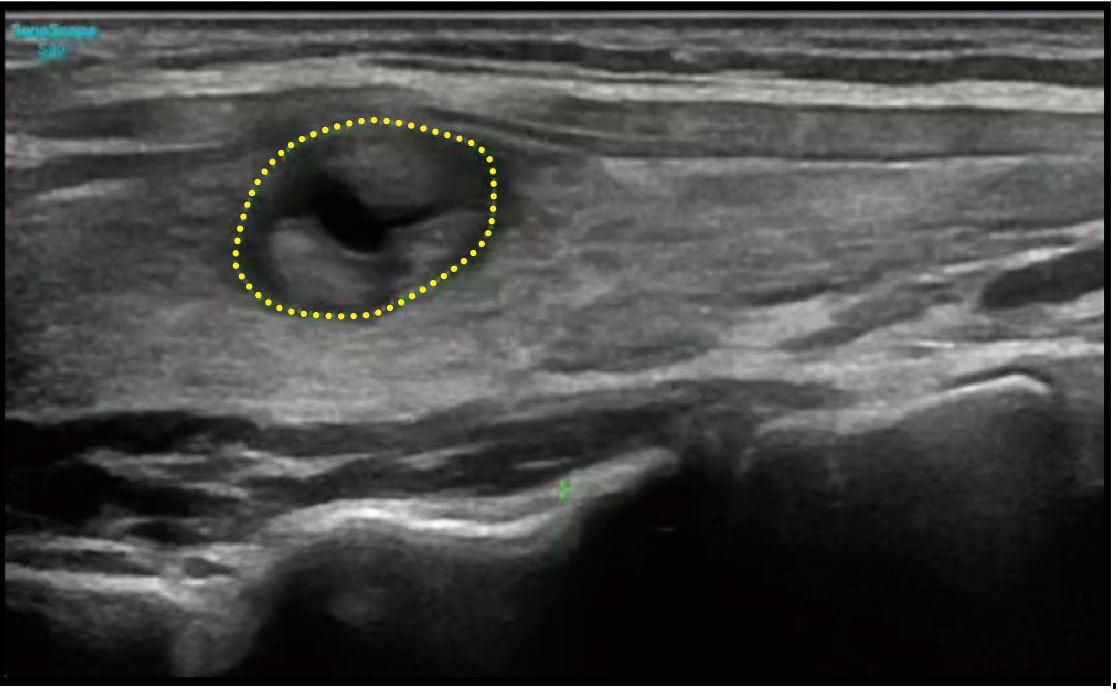

ATI (Akustik Zayıflama Görüntüleme), zayıflama katsayısını ölçerek karaciğer steatozunun nicel değerlendirilmesini sağlar ve klinisyenlerin steatoz derecesini değerlendirerek güvenilir bir prognostik tahmin yapmalarına yardımcı olur.